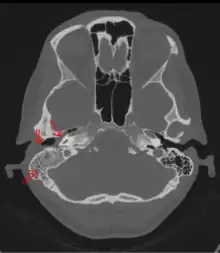

Un examen de la cabeza puede revelar signos de mastoiditis. Los siguientes exámenes pueden mostrar una anomalía en el hueso mastoideo:

- Tomografía computarizada del oído

- Tomografía computarizada de la cabeza

- Radiografía del cráneo. Un cultivo del drenaje del oído puede revelar presencia de bacterias.